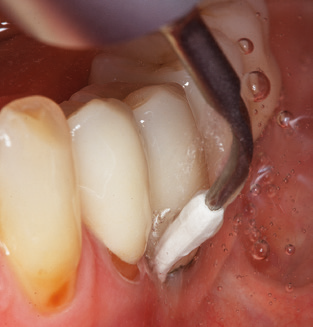

Of course, working tips for the cleaning of implant surfaces are also indispensable for SPT in patients fitted with implants. The implant cleaning attachment on the system used here is characterised by its tapered, hexagonal design. This design allows light, atraumatic penetration of the peri-implant pocket and displays a good cleaning performance (Fig. 7).

Fig. 4: Flexible probes with millimetre markings are recommended for the probing of dental implants (e.g. Colorvue Kit PCV11KIT6, Hu­Friedy). – Fig. 5a and b: A straight working tip (1P, W&H Dentalwerk Bürmoos GmbH) is a suitable instrument for use on all natural teeth. – Fig. 6: Curved working tips (3Pr/3Pl, W&H Dentalwerk Bürmoos GmbH) lend themselves to the processing of difficult-to-reach areas of the tooth and root surfaces (e.g. furcations). – Fig. 7: The tapered, hexagonal implant cleaning tip (1I, W&H Dentalwerk Bürmoos GmbH) permits atraumatic and efficient cleaning of the crown and abutment surfaces. – Fig. 8: Titanium and carbon curettes are suitable instruments for the manual cleaning of the implant surfaces.